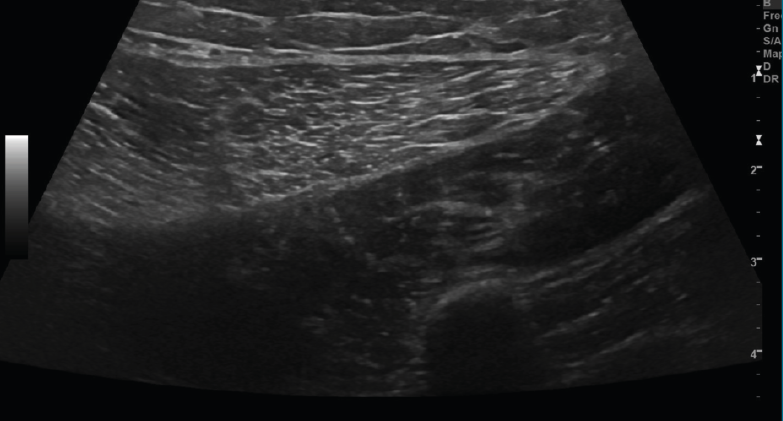

4. Bultomas

Se observa una colección hipo- o anecoica con refuerzo acústico en lesiones líquidas y sin refuerzo acústico en lesiones sólidas. También puede ser hiperecoica en casos de contenido graso (Figuras 15, 16 y 17).